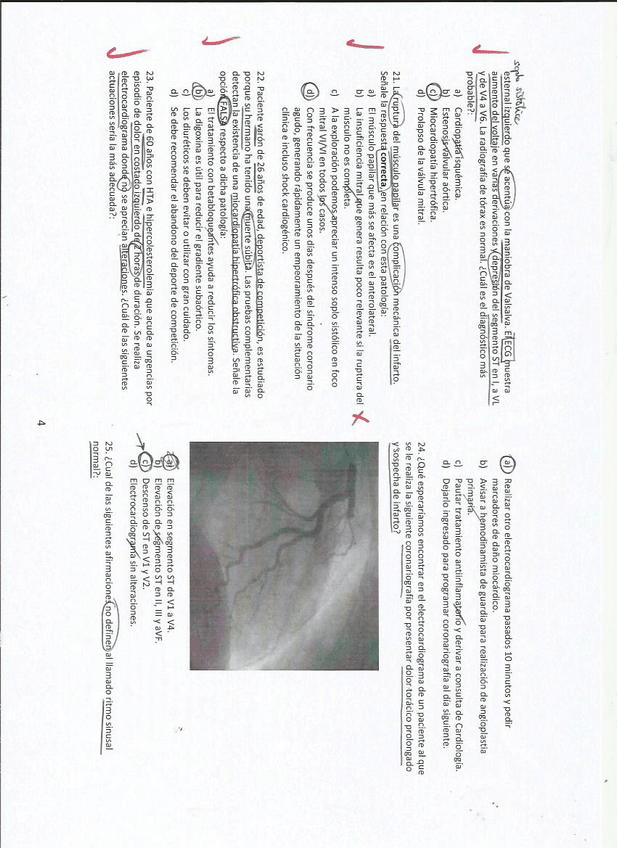

EXAMEN CARDIO 2019-2020

He publicado nuevos examenes de 4º Patología Cardiocirculatoria: EXAMEN CARDIO 2019-2020